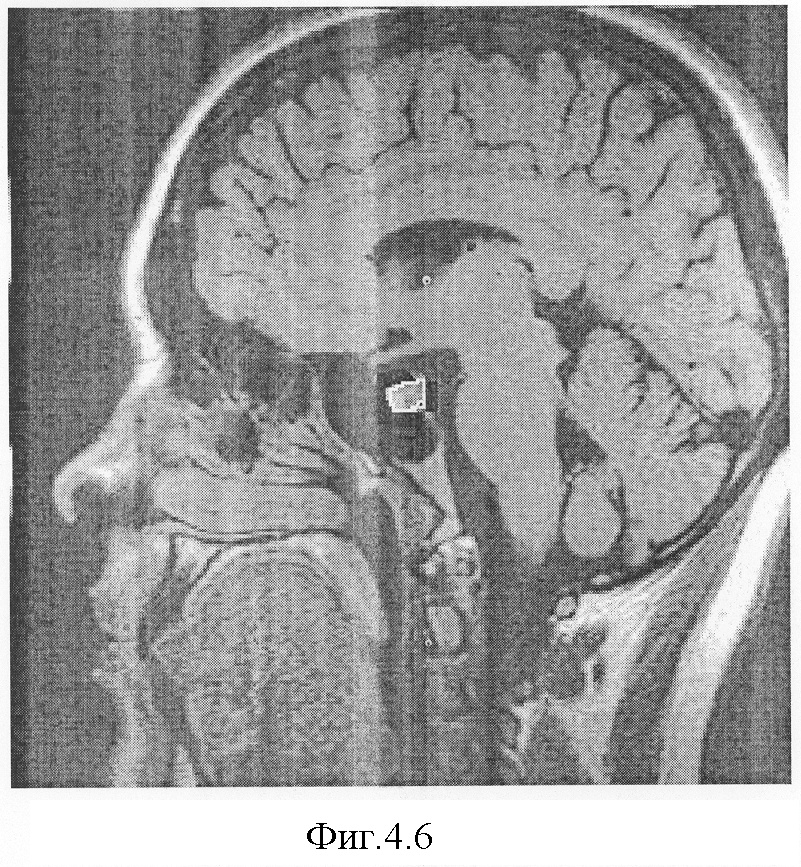

На фиг.4.1-7 показаны результирующие семь изображений, проходящие в сагиттальной плоскости через гипофиз. При этом фиг.4.1 проходит в непосредственной близости от турецкого седла справа, через сифон внутренней сонной артерии, гипофиз не затрагивает;

фиг.4.6 – краевой сагиттальный срез через гипофиз слева, площадь, обведенная по гипофизу, равна 0,3 см2.